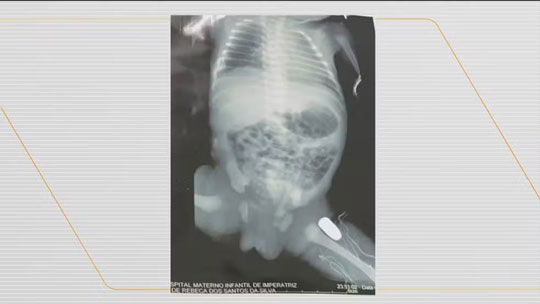

Grávida é baleada e projétil fica alojado na perna do bebê

Uma adolescente de 15 anos, grávida de nove meses teve que fazer um parto de emergência, após ter sido atingida por uma bala durante um assalto em Imperatriz, a cerca 631 km de São Luís. O crime aconteceu na noite de domingo (16).

De acordo com a Secretaria Estadual de Saúde (SES), o estado de saúde da vítima é estável e o bebê deve ser operado ainda nesta segunda-feira (17) para retirar a bala que ficou alojada na perna.